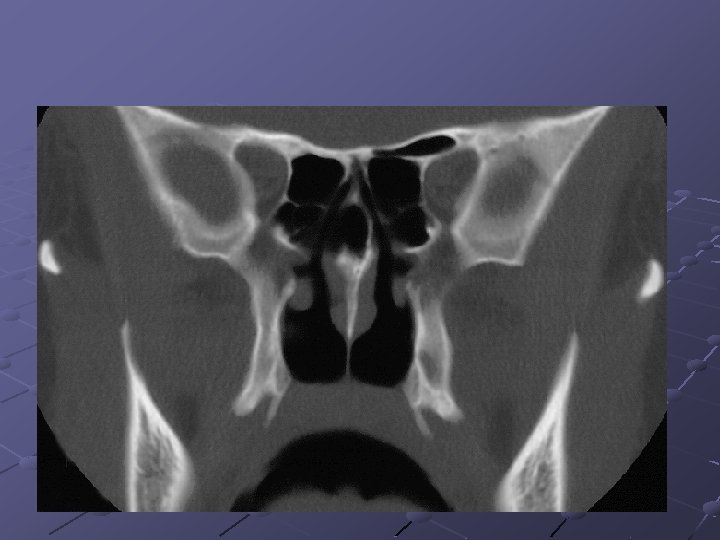

CRS 78 had criteria to CRS 17 endoscopy: positive 37 - CT findings: positive 6 endoscopy : positive 41 - CT findings: negative 35: endoscopy negative & CT negative 20: endoscopy negative & CT positive 55: endoscopy negative Stankiewicz & Chow: Otolaryngol Head Neck Surg 2002

Radiology & clinical exam Correlated with a Sensitivity of 75% And specificity of 84% Endoscopy correlated poorly with sinus disease and not predictive Stankiewicz & Chow: Otolaryngol Head Neck Surg 2002

Endoscopy/ct findings/clinical Easy to diagnose CRS by endoscopy alone when nasal polyps, purulence, or fungus is observed, when absent, establishing the diagnosis may be more difficult 45% of patients with clinical CRS were both endoscopically and radiographically negative. Stankiewicz and Chow. Otolaryngol head neck surg 2002

Endoscopy/ct findings/clinical Negative endoscopy alone is insufficient to rule out sinusitis. 26% of patients who were negative on endoscopy had positive CT – this would suggest that if endoscopy is negative most of the time the ct will be also negative, even with a positive history. Stankiewicz & Chow: Otolaryngol Head Neck Surg 2002

The surgical site in children There is strong evidence to support the fact that the OMC area is the primary site of involvement of inflammatory sinuses disease.